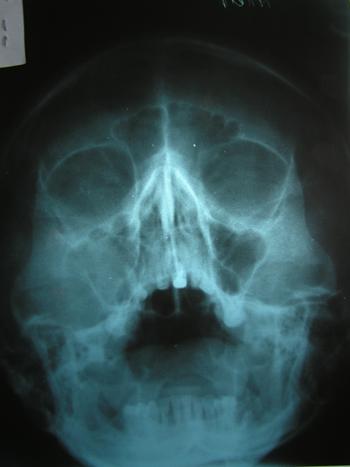

4. Examenul radiografic. Intrucat manifestarile clinice ale chisturilor maxilare sunt comune si pentru multe tumori ale oaselor maxilare, examenul radiografic are o importanta majora pentru conturarea diagnosticului. Permite totodata depistarea chisturilor in stadiu endoosos, profund, inainte de a deveni perceptibile clinic. Examenul radiografic pune in evidenta extensia formatiunilor chistice, raporturile lor cu dintii si cu celelalte structuri anatomice (fose nazale, sinus maxilar, canal mandibular), furnizand astfel elemente pretioase privind indicatiile de tratament si tehnica operatorie adecvata. Radiografia da indicatii in ceea ce priveste pastrarea dintilor prin rezectie apicala sau extractia lor, precizand extinderea rezorbtiei osoase a procesului alveolar si lungimea radacinii ramase in os sanatos.

Se indica: - radiografie in incidenta retroalveolara sau ocluzala pentru chisturile mici sau pentru clarificarea relatiei leziune-dinti in cazul chisturilor mai voluminoase;

- ortopantomografie;

- radiografii ale sinusurilor anterioare ale fetei (SAF)

Imaginea clasica a chisturilor maxilare este de radiotransparenta rotunda sau ovalara bine delimitata de o banda de osteocondensare marginala.

5. Tomografia computerizata este o metoda imagistica eficienta pentru evaluarea leziunilor osoase maxilo-faciale, adesea fiind dificila stabilirea exacta a extinderii distructiei osoase si gradul de afectare a structurilor adiacente printr-un examen radiolografic clasic. De asemenea, diferentiaza un proces chistic de unul solid, surprinzand chiar transformarile tumorale care pot sa apara intr-o leziune chistica. Pentru evidentierea localizarii si a raporturilor leziunilor osoase cu tesuturile adiacente este necesar sa fie practicat atat in sectiuni axiale cat si biaxiale.